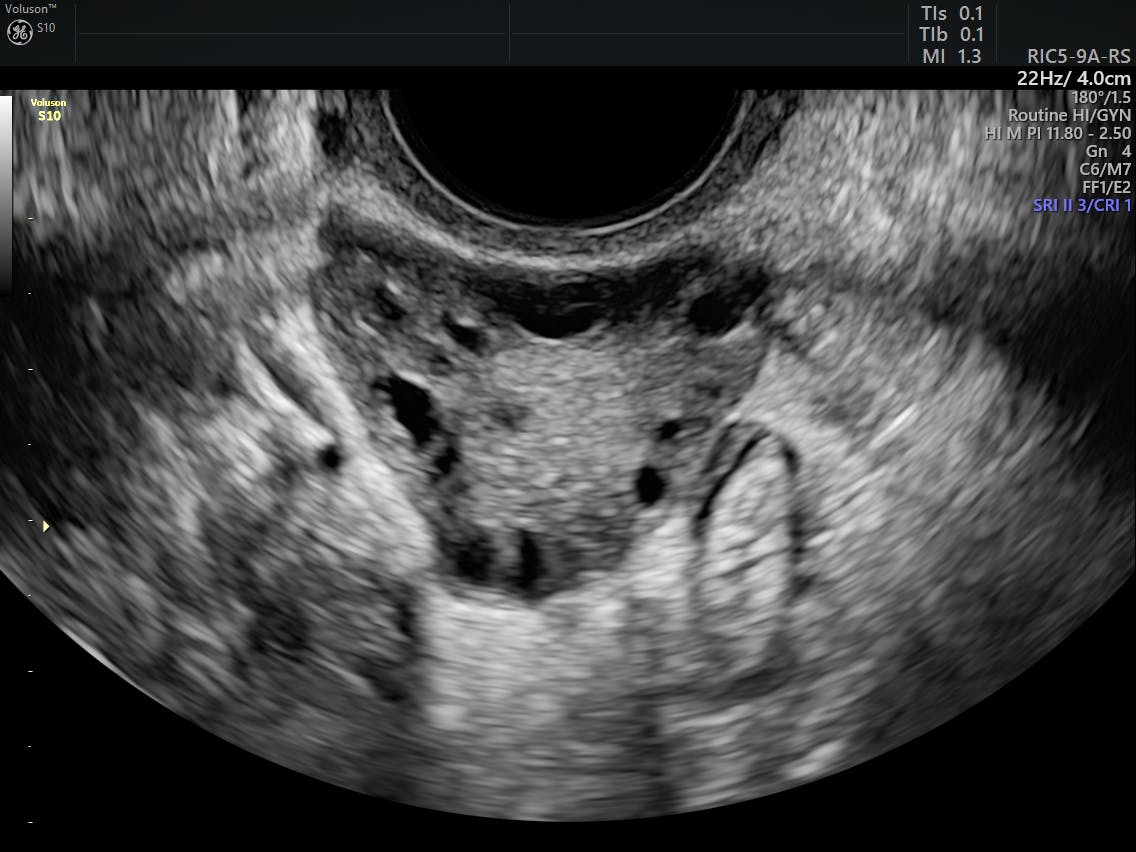

Anovulation/oligoovulation, hyperandrogenism, and polycystic ovaries revealed by sonogram. The rotterdam criteria17 have suggested a broader definition for pcos, with two out of three of the following criteria being diagnostic of the condition: Polycystic ovaries (either 12 or more follicles or. The rotterdam criteria mandate the presence of 2 of the following three findings: The rotterdam criteria mandate the presence of 2 of the following three findings:

Les critères de rotterdam aident au diagnostic du syndrome des ovaires polykystiques (sopk). According to the rotterdam criteria, which are widely used for diagnosis,10 controversy in clinical endocrinology: Ils ne s'appliquent pas vraiment au diagnostic du sopk ches les adolescents. Prior to following this criteria, it is essential to exclude other aetiologies like hyperprolactinemia. The rotterdam criteria require any two of the following three conditions for diagnosis: Oligo/amenorrhea, clinical or biochemical hyperandrogenism. Polycystic ovaries (either 12 or more follicles or. Sentinel node tumor burden according to the rotterdam criteria is the most important prognostic factor for survival in melanoma patients. Download scientific diagram | rotterdam criteria for diagnosis of pcos (2). The rotterdam criteria17 have suggested a broader definition for pcos, with two out of three of the following criteria being diagnostic of the condition: The rotterdam criteria for polycystic ovary syndrome. Anovulation chronique (oligoménorrhée / aménorrhée). Ultrasound criteria in the diagnosis of polycystic ovary syndrome (pcos).

We endorse the rotterdam pcos diagnostic criteria in adults (two of clinical or biochemical hyperandrogenism, ovulatory dysfunction, or polycystic ovaries on ultrasound) and where. Criteria rotterdam encompass three of the most common symptoms of women with pcos. Anovulation chronique (oligoménorrhée / aménorrhée). The rotterdam criteria have been used to guide research and predict reproductive prognosis, but there is some debate as to whether this consensus opinion guides. Polycystic ovaries (either 12 or more follicles or. The rotterdam criteria require any two of the following three conditions for diagnosis: One, the most commonly used diagnostic criteria used for pcos—the rotterdam criteria—indicates that either biochemical or secondly, also according to the rotterdam criteria, you don't have to. Ultrasound criteria in the diagnosis of polycystic ovary syndrome (pcos).